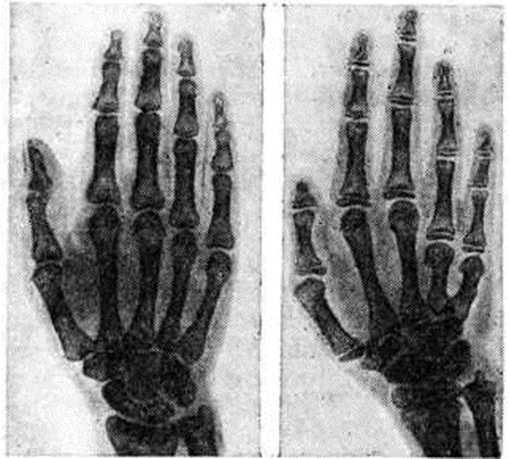

Возрастная дифференцировка скелета при допубертатной форме Гипогонадизм, как правило, запаздывает. Наблюдается неравномерный рост метаэпифизарных зон фаланг кистей, лучевой и локтевой костей, выражающийся в образовании различной формы и величины углублений и выступов, а также субхондральном склерозе. Характерно удлинение и некоторое истончение костей конечностей. У больных первичным Гипогонадизм, связанным с генетической патологией (смотри Тернера синдром), встречаются аномалии развития скелета (напр., укорочение фаланг IV—V пальцев кистей и стоп, укорочение IV и V пястных костей) — положительный метакарпальный синдром (рисунок), деформация Маделунга, врождённые клиновидные позвонки, веерообразное слияние рёбер, деформации грудины и медиальных мыщелков большеберцовых костей. ЛечениеПри первичном Гипогонадизм, начиная с пубертатного возраста, показана постоянная заместительная терапия половыми гормонами (в прошлом опотерапия). Мужчинам вводят препараты с андрогенной активностью, женщинам — эстрогены (до появления индуцированных менструаций), в дальнейшем переходят на комбинированную терапию эстрогенами и гормонами жёлтого тела. При вторичном Гипогонадизм проводят лечение гонадотропинами, при необходимости — в комбинации с половыми гормонами, по показаниям — кломифенцитрат (смотри). Препараты, их дозы и метод введения подбирают индивидуально в зависимости от формы заболевания, возраста больного и выраженности симптомов Гипогонадизм; необходимо проводить лечение также основного заболевания. Хирургическое лечениеПопытки замещения нефункционирующей (или отсутствующей) половой железы функционально активной (от донора или трупа) производили ещё в конце прошлого века. Развитию этого направления в лечении Гипогонадизм способствуют совершенствование хирургической техники, методов консервации органов, изучение совместимости тканей и изыскание активных иммунодепрессантов. Операция пересадки яичников и яичек довольно сложна, требует владения техникой шва на сосудах малого калибра. Половую железу донора берут с сохранением сосудистой ножки (дистальная ветвь от a. uterina к яичнику или a. etv. testicularis к яичку). Анастомоз сосудов пересаживаемой половой железы производят либо с ветвями бедренной артерии и вены, либо с нижней надчревной артерией и веной, при сохранении семенного канатика реципиента — с a. etv. testicularis. Яичко может быть фиксировано в мошонке, под кожей живота или с внутренней поверхности бедра; яичник фиксируют под кожей бедра. При недоразвитии полового члена делаются попытки пластически его реконструировать. Варианты операций сводятся к формированию филатовского стебля при сохранении тканей полового члена для обеспечения эротогенной чувствительности при половом сношении (смотри Coitus). Иногда с косметической целью применяют подсадку синтетических пластических материалов («яичко») в мошонку (с целью имитации наличия яичка). Прогноз для жизни благоприятный. Однако при отсутствии лечения нарастание комплекса неполноценности может привести в некоторых случаях к суицидальным попыткам. При систематическом лечении достигается развитие вторичных половых признаков, появляются индуцированные менструации, либидо, потенция, обеспечивается возможность половой жизни, исчезают сопутствующие явления (остеопороз, отставание в формировании скелета и так далее).